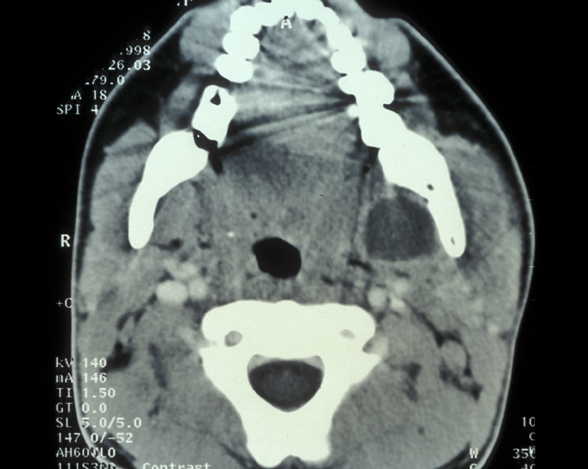

An abscess may remain localised and drain via a small intraoral sinus (a ‘gum boil’, see Figure 1) or may spread giving rise to a severe cellulitis involving multiple tissue spaces (a cervicofacial abscess, see Figure 2).

Figure 1: An example of a localised abscess.